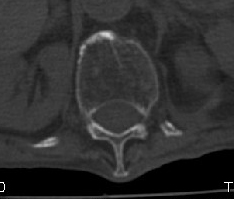

男:89岁因外伤后2天行ct检查。请各位战友讨论图中所指是否是骨折和形成该影像的原因(扫描层面位于椎体中份)。

如有楔形变,考虑压缩性骨折,陈旧性,腰椎退行变。

考虑压缩性骨折,腰椎退行变。

椎体压缩性骨折,结肠淤张,胀气说明肯定骨折.

椎体压缩骨折,结肠淤张,应该肯定,交感神经有损伤.

老年性骨质疏松症、压缩性骨折,退行性变。

骨质疏松,考虑陈旧压缩性骨折.(有硬化边).